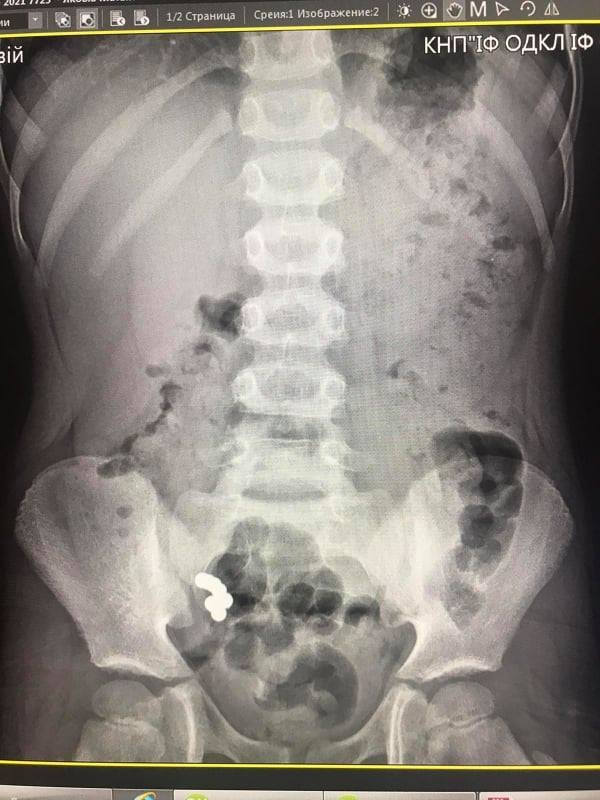

Нещодавно в хірургічне відділення обласної лікарні поступив хлопчик віком 5 років через 17 днів після ковтання дрібних магнітних кульок. При госпіталізації скарги були відсутні. Під час рентгенологічного дослідження діагностовано наявність магнітів в кишечнику, які не просуваються впродовж 10-ти днів. Відсутність пасажу магнітів о кишечнику стало показанням до оперативного втручання.

Під час операції виявлено інтимне зрощення стінки тонкої кишки, де розташовані 4 магніти, зі стінкою сліпої кишки, де виявлено 3 магніти. Тож, медики провели клиновидну резекцію тонкої та сліпої кишки, видалення магнітів, ушивання стінки тонкої та сліпої кишки.